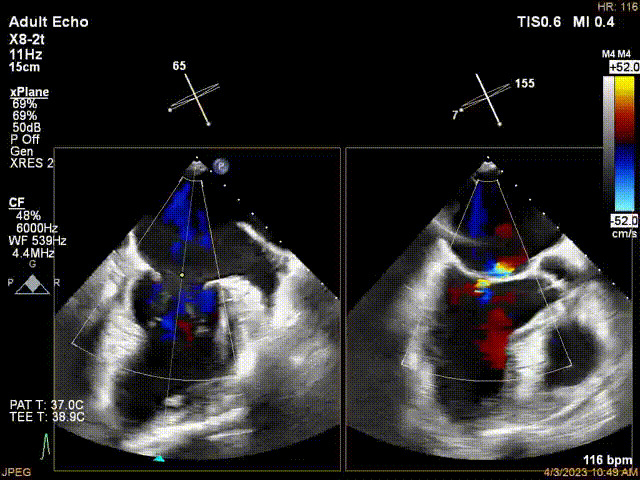

接受治療的是一例器質性重度二尖瓣反流(DMR)患者,主訴“反復活動后胸悶,氣促3年余”。術前超聲顯示,雙房增大,二尖瓣脫垂伴重度反流,輕度三尖瓣反流,輕度肺高壓,升主動脈增寬。手術經股靜脈-房間隔入路,采用全身麻醉插管,在TEE和DSA引導下完成房間隔穿刺。置入JensClip瓣膜夾系統后,在左房調整瓣膜夾的位置和軸向,后進入左室,在TEE引導下捕捉二尖瓣前后瓣葉,并關閉瓣膜夾。經TEE反復確認手術效果后最終鎖定并釋放瓣膜夾。術后即刻超聲顯示瓣膜夾位置穩定,功能良好,術前二尖瓣反流4+,術后0反流,肺靜脈逆流和左房壓都顯著好轉,手術圓滿成功(以上數據都來源于醫院的臨床記錄)。術后患者狀態良好,目前已安排出院。

術前超聲提示二尖瓣重度反流